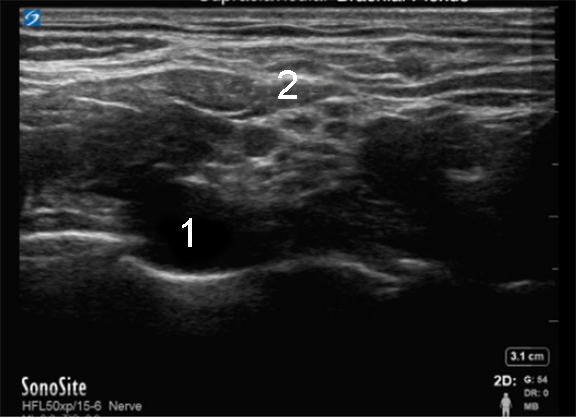

Supraclavicular Nerve Block Pre-Injection Image

Subclavian Artery

Brachial Plexus